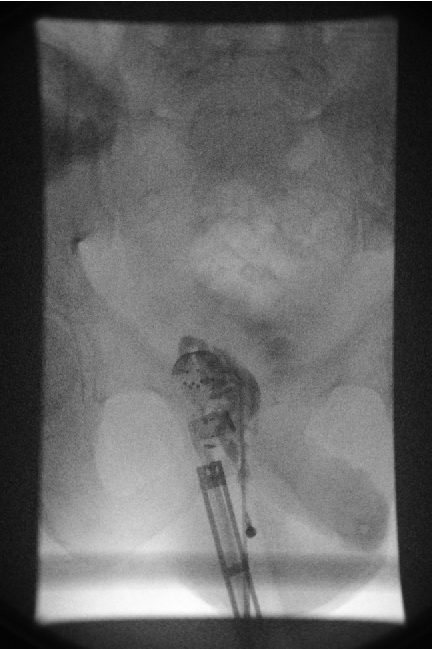

Needle, guidewire, sheath and catheter could all be placed into the seminal vesicle as demonstrated by CT-Imaging (Figure 3 [Fig. 3]). The guidewire coiled within the lumen of the seminal vesicle and we did not achieve to steer the guidewire through the ejaculatory duct to achieve a through-and-through access to the penile urethra. Therefore, we were not able to proceed to insertion of a balloon-catheter over the guidewire in a subsequent retrograde approach.

Figure 3: A 17 mm maximum intensity projection of a CT-Scan shows a guide-wire coiled within the lumen of the right seminal vesicle and an angiographic catheter sheath inserted into the seminal vesicle.